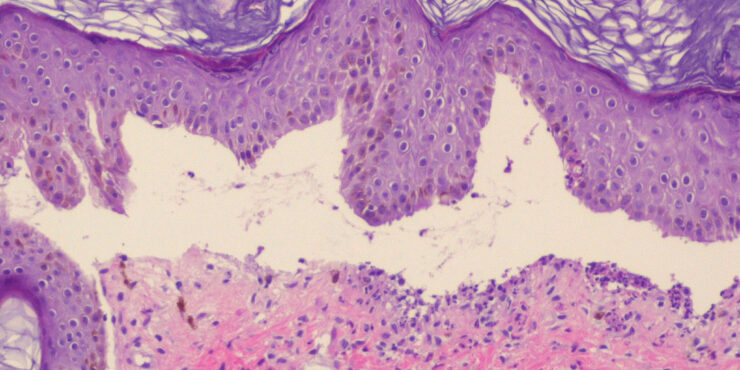

Branchial cleft cyst =كيسة الشق الغلصمي Branchial Cyst (Branchial Cleft Cyst) Sequestration of first or second branchial cleft membranes results in these cysts, sinuses, or tags. EPIDEMIOLOGY Branchial cleft cysts are largely sporadic, but autosomal dominant cases have been reported. There is no gender predominance. Ten percent of lesions are bilateral. ETIOLOGY AND […]